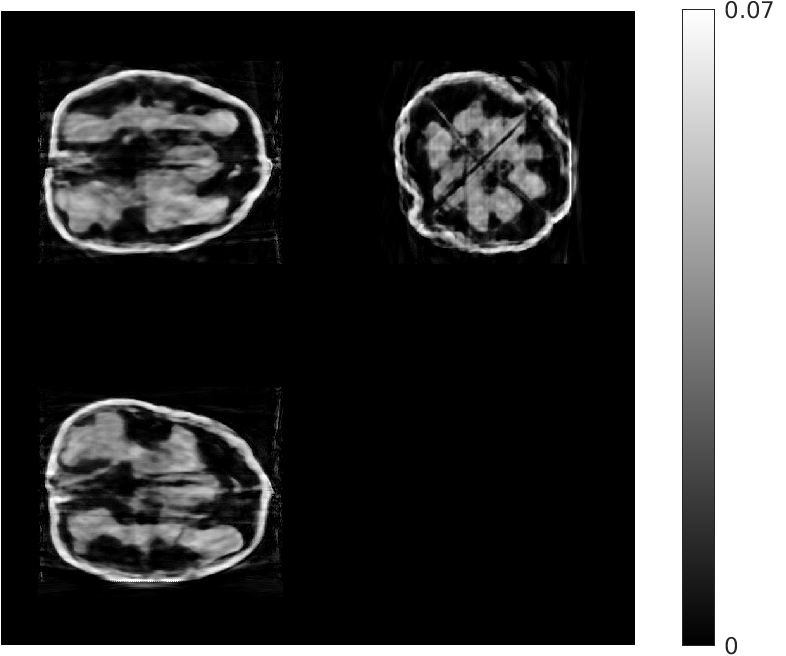

Fig. 4 shows the results of the intermediate steps of the first stage of our reconstruction for walnut 2 (8 views) in the test dataset. While the patch-based destreaking compensates for the blurring introduced by the EP-regularized reconstruction and ‘fills-in’ details in the reconstructed volume, the data-consistency plays a key role in mitigating hallucinations introduced by the CNN, and reinforces image features that are consistent with the acquired measurements.

| Input EP Recon. | Post CNN-based Destreaking | Post Data-consistency |

![]() |

| (NMAE:0.45) | (NMAE:0.38) | (NMAE:0.32) |